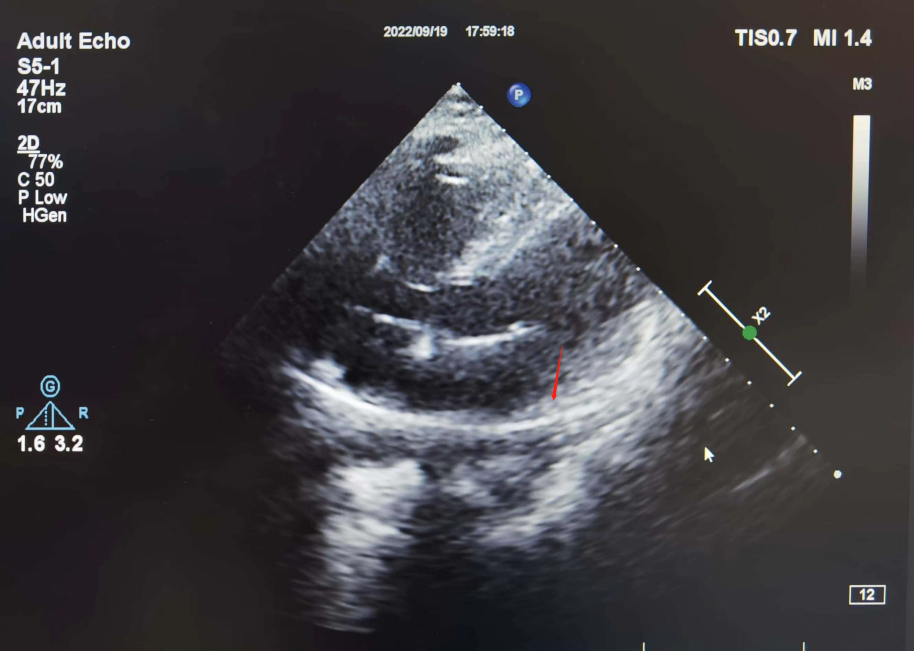

手术电极是什么意思超声引导,东莞市人民医院心内科团队“零射线”植入心系列双腔起搏器_https://www.jmylbn.com_新闻资讯_第4张

彩超下观察心室电极导线的位置